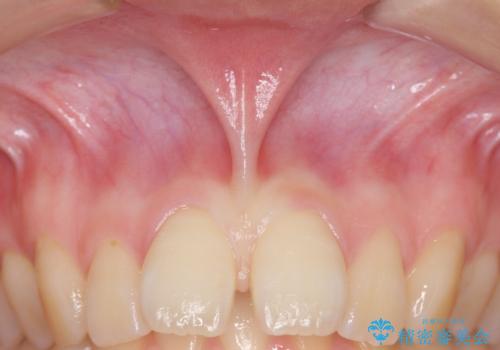

上唇小帯切除 矯正前の予防的外科処置

上唇小帯切除 矯正前の予防的処置